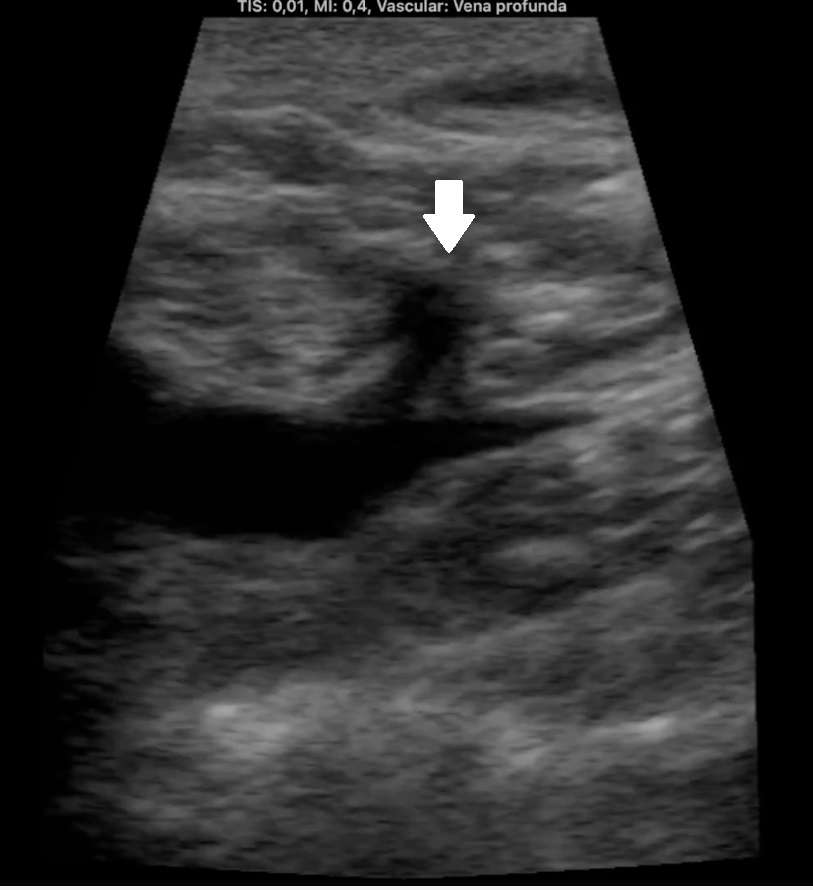

Hombre de 68 años con antecedentes de hernia de hiato/gastritis/úlcera duodenal, ex fumador desde hace 9 años y colelitiasis. Acude por edema y empastamiento de MID de 4 días de evolución (Imagen 1). Pérdida de peso de 5 kg en 2 meses. Analítica 20 días antes antes con Hb 14, LDL 150 y GGT 59, resto normal.

Ocupación de espacio con trombo venoso ecogénico desde poplítea hasta tercio superior, así como safenas externa e interna (imagen 2 femoral profunda e imagen 3 safena mayor). Lesión isoecogénica en segmentos hepáticos V/VI de 6,65 x 5,87 cm (imagen 4).